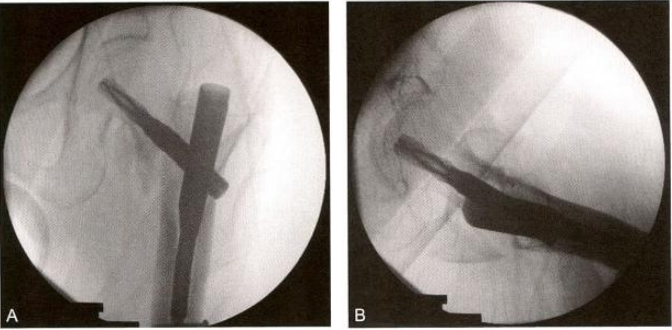

图9-8 用克氏针对移位的骨折块进行撬拨复位。A.前后位X 线影像示左股骨转子间 骨折,内翻移位,伴股骨大转子骨块骨折, AO-OTA分型31A2.3;B. 牵引后近端仍 然存在外旋,大转子移位明显;C. 侧位透视显示大转子骨块向前移位;D. 将大转子推 顶复位,用克氏针将其与近端骨折端固定;E. 侧位透视显示大转子骨折块复位良好, 克氏针位于后侧,不影响主钉插人